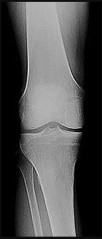

Question 12:

Following a primary total knee arthroplasty, a patient experiences isolated patellar clunk syndrome. Which of the following implant designs or technical factors is most closely associated with this phenomenon?

Correct Answer: Posterior-stabilized (PS) femoral component with a high intercondylar box

Explanation:

Patellar clunk syndrome occurs in posterior-stabilized TKA when a fibrotic nodule forms at the superior pole of the patella. During extension, this nodule catches in the intercondylar box of the femoral component and "clunks" out as the knee reaches full extension.